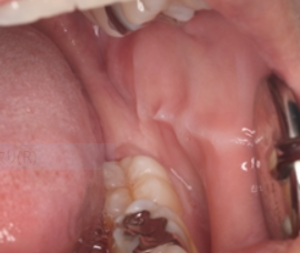

骨隆起

舌圧痕

頬圧痕